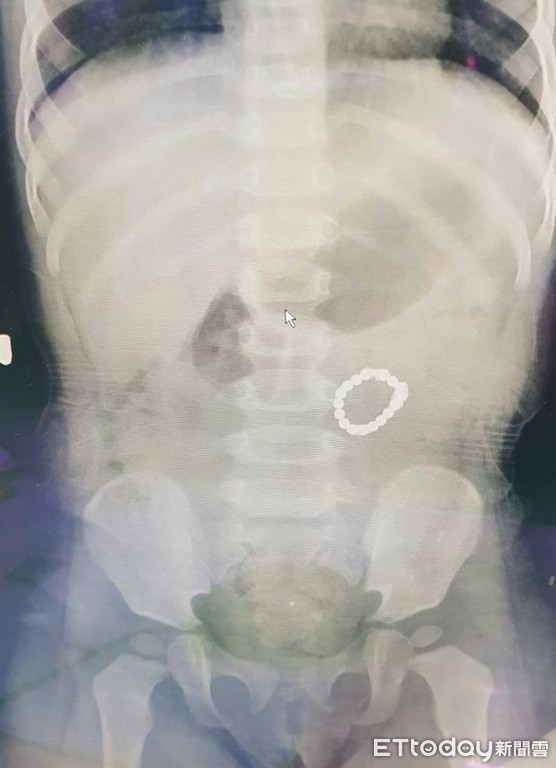

▲X光片可看到,女童腸道內有一串手珠。(圖/童綜合醫院提供)